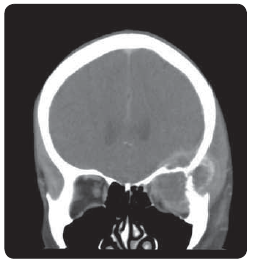

50letá pacientka, dosud interně nestonající, bez onkologické rodinné anamnézy, byla přijata na GPK FN Plzeň pro měsíc trvající bolesti břicha. Pro nález cystického útvaru na levém ovariu byla provedena hysterektomie s oboustrannou adnexektomií. Histologie útvaru vycházejícího z appendixu a prorůstající do ovaria byla IHC pozitivní na AE1/ 3 a chromogranin. V druhé době byla provedena pravostranná hepatektomie pro metastatické postižení. U pacientky bylo v plánu podání systémové léčby, ale v první době bylo nutné dořešení nálezu megaureteru vpravo. Indikována nefrektomie. Nově se objevili potíže charakteru exophtalmu a deprese bulbu levého oka. Provedeno kontrolní CT orbity s nálezem expanze charakteru metastázy v levé očnici. Následně provedeno CT břicha s nálezem masivní generalizace v průběhu colon ascendens a hepatálního ohbí, lymfatických uzlin retroperitonea, podél pánevních svazků vlevo a na resekční ploše jater. Při maximálních obtížích způsobených metastázou v orbitě byla indikována konkomitantní chemoradioterapie. Zahájena systémová léčba kapecitabinem a pro karcinoidové projevy zahájena léčba lanreotidem. Přes provedenou léčbu lokální nález progredoval a objevily se bolesti, které si vyžádaly léčbu opiáty. Pacientka umírá sedm měsíců od operace.